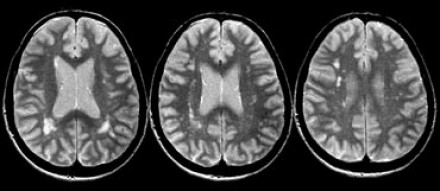

多發(fā)斑塊狀病灶的鑒別診斷

圖片一

在上圖中,是各種多發(fā)性點狀和斑塊狀白質(zhì)病灶圖像,我們對其中部分病例進行詳細討論。需要說明的是,以下鑒別診斷中提到的疾病與上圖中的圖像并不完全重合。

交界區(qū)腦梗死

MRI成像病灶要點:一般來說,這些病灶僅位于一個腦半球,要么位于深層白質(zhì)與灰質(zhì)的分水嶺區(qū)域(watershed area),要么位于周圍的分水嶺區(qū)域。在上圖中,病灶位于深層的分水嶺區(qū)域。

急性播散性腦脊髓炎(ADEM)

MRI成像病灶要點:在感染或接種疫苗后10-14天,多個局灶性病灶出現(xiàn)在腦白質(zhì)和基底節(jié)。與MS一樣,ADEM病變可累及脊髓、U形纖維以及胼胝體,有時可出現(xiàn)增強病灶。與MS所不同的是,ADEM的病灶通常更大,且好發(fā)于青年人,病程是單相的。

萊姆病

病灶大小約為2-3毫米,與MS的病灶相似,但患者會有皮疹和其他流感樣疾病。脊髓呈現(xiàn)高信號,CN7(神經(jīng)根入腦干區(qū))信號增強。

肉樣瘤

肉樣瘤的病灶分布與MS非常相似。

進行性多灶性白質(zhì)腦病(PML)

PML是一種由JC病毒感染引起的脫髓鞘性疾病,常見于免疫抑制患者。

MRI成像病灶要點:白質(zhì)損傷病灶在U形纖維的間隙占位,不增強,與HIV或CMV不同。

PML的病灶可在單側(cè)出現(xiàn),但更常見的是呈雙層、不對稱性分布。

血管周圍間隙(Virchow Robin spaces)

MRI成像病灶要點:T2加權(quán)成像明亮,F(xiàn)LAIR成像黑暗。

小血管性疾病

白質(zhì)損傷病灶位于深層白質(zhì)區(qū)域,不位于胼胝體、腦室旁或皮層旁。